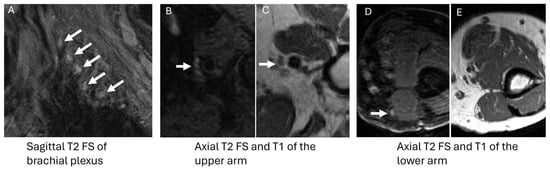

3.2. AL Amyloidosis